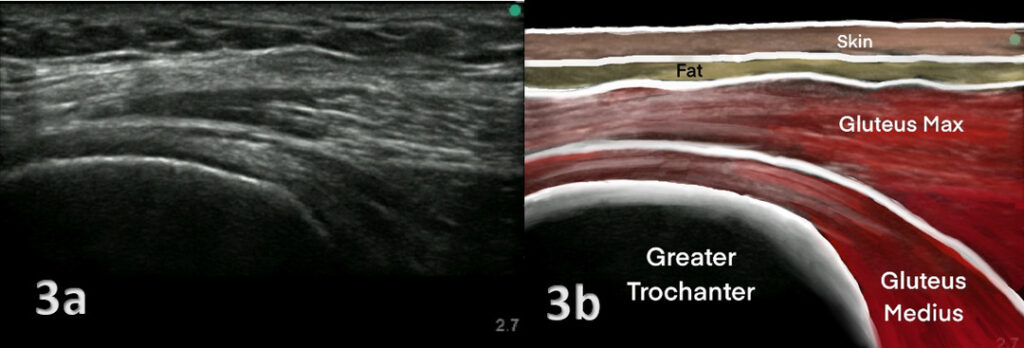

- Ultrasound: An ultrasound scan can be used to detect bursitis or damage to the gluteal tendons.

Imaging Tests:

- X-Rays: X-rays can help rule out other causes of hip pain, such as fractures or arthritis.

- MRI (Magnetic Resonance Imaging): An MRI provides detailed images of the soft tissues, tendons, and bursae. It can reveal inflammation, tendon tears, or degeneration.